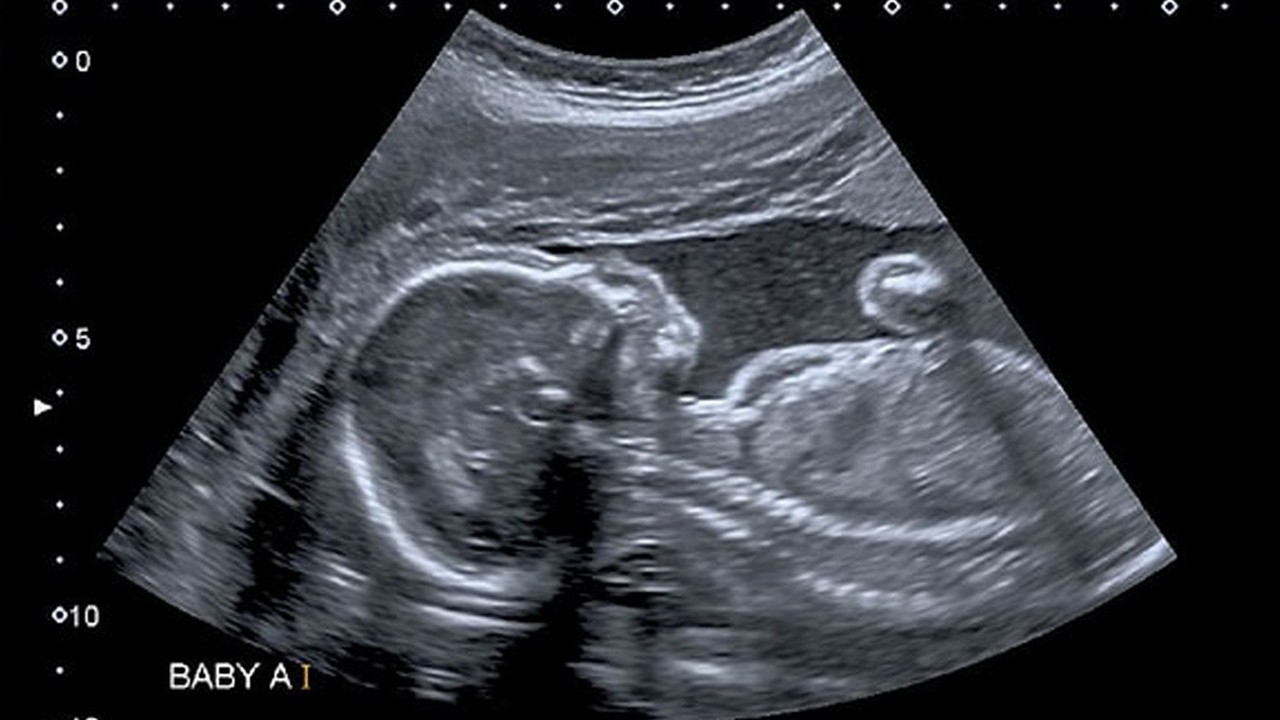

CNN televizyonunun haberine göre, Boston Çocuk Hastanesi'nden bir grup doktor, türünün ilk örneği olan beyin ameliyatını çocuk henüz anne karnındayken başarıyla gerçekleştirdi.

Doktorlar, "Galen ven malformasyonu" adı verilen, nadir ortaya çıkan hastalığı bebek 30 haftalıkken tespit etti.

ABD'de "Stroke" adlı bilim dergisinde yayımlanan ve alanında ilk olduğu belirtilen ameliyat, ultrason kullanılarak atardamarın tespiti yöntemiyle gerçekleştirildi.

Doktorlar, annenin karnından uzun bir iğneyi bebeğin beyninin etkilendiği kısma yönlendirmek için ultrason kullandı. Doktorlar, daha sonra damarlara geri akışı engellemek amacıyla damarın içine bir madde enjekte etti.